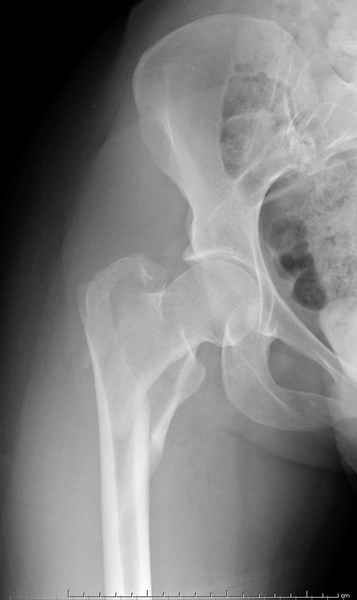

Уважаемые коллеги.Ко мне обратился мой коллега, весьма опытный травматолог, владеющий практически всеми видами остеосинтеза, с просьбой собрать мнения по поводу нескольких клинических случаев - два перелома бедра и перелом плеча.Если можно, подтвердите свое мнение иллюстрациями аналогичных ситуаций, либо ссылками - для клинического разбора. Бедро 1:Женщина 1929 г.р. Травма в результате падения 14.09.04г.Диагноз Закрытый оскольчатый чрезвертельный перелом правой бедренной кости со смещением отломков.Сопутствующие заболевания: ИБС, стенокардия напряжения, постинфарктный кардиосклероз (ИМ в 1992 году); гипертоническая болезнь 2 ст.; ожирение 3. Дополнительные данные - сохранная старушка.Спасибо.С уважением Александр Артемьев

Типичный остеопорозный вертельный перелом , не стабильный, 4-х фрагментный, базоцервикальный. Лечение оперативное не позднее 48 часов после перелома, чем раньше тем лучше, если общее состояние позволяет.

Фиксатор или DHS 130 градусов или PFN с короткой ножкой. Если DHS, то шуруп должен находиться в центре шейки и дополнительно еще простой длинный шуруп против ротации в проксимальной части шейки над шурупом DHS. Полную нагрузку на ногу начать через 6 недель.